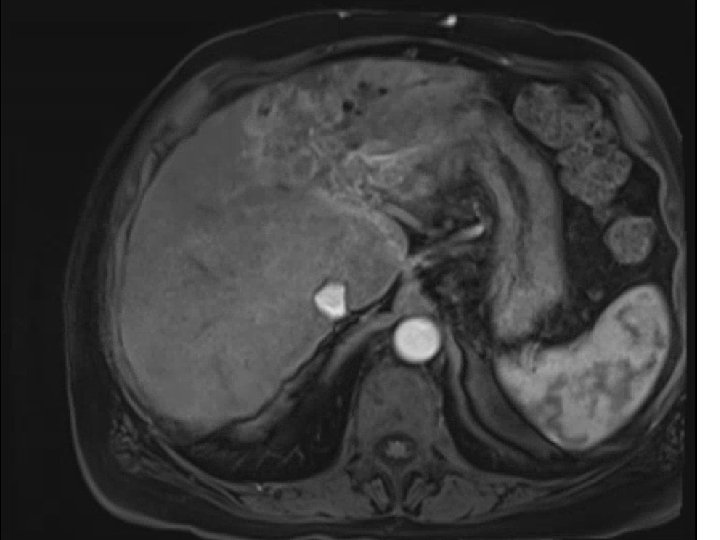

• 74 y. o. male with a large left lobe HCC involving Segment

• 74 y. o. male with a large left lobe HCC involving Segment II, III, and IV also with left portal vein thrombosis. Biopsy confirmed at OSH as moderately differentiated HCC. BCLC stage C tumor. Child-Pugh A with an ECOG PS of 0. Patient presented to MGH for consideration of radioembolization. Patient did not desire chemotherapy due to significant side-effects

Pre-presentation MRI